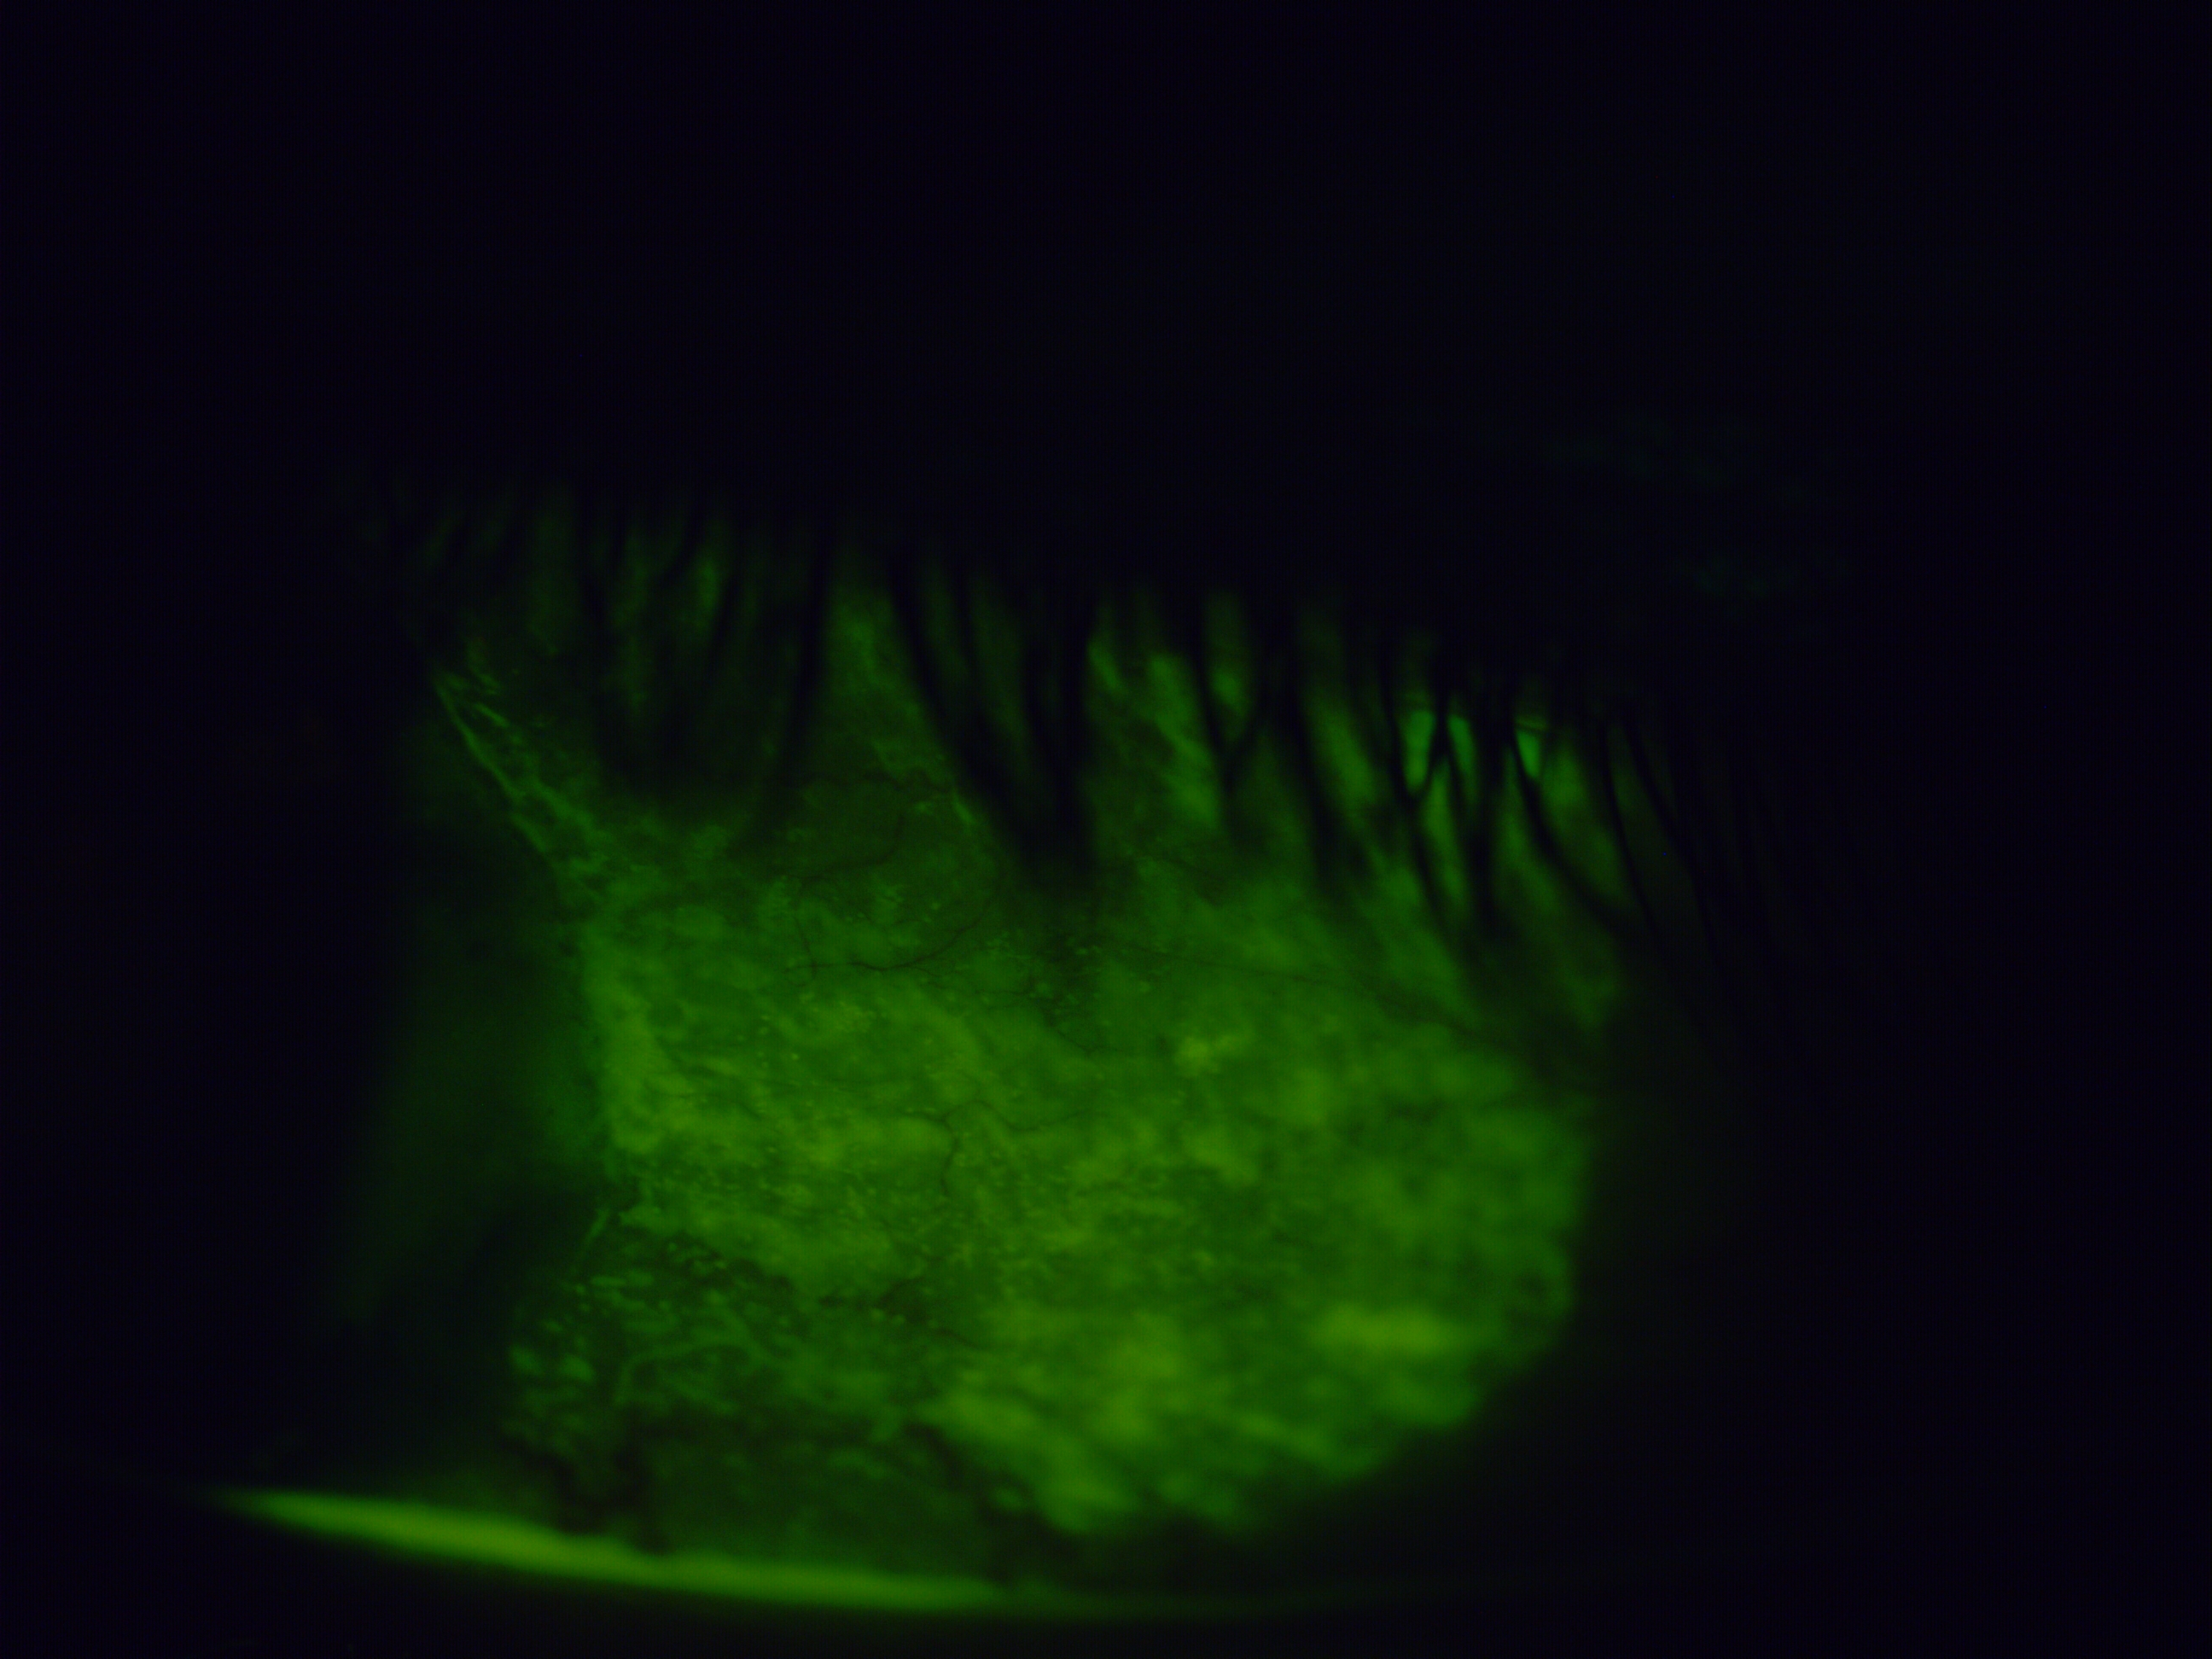

The images below were taken on presentation using fluorescein dye under cobalt blue light — damaged areas of the eye's surface absorb the dye and fluoresce brightly, showing the extent of the problem directly.

The improvement to the surface integrity is visible directly in the fluorescein image taken one week after removal — and reflected in the patient's symptoms. The chronic redness, the surface staining, and the subjective discomfort all showed meaningful improvement, with further gradual recovery continuing in the weeks that followed.